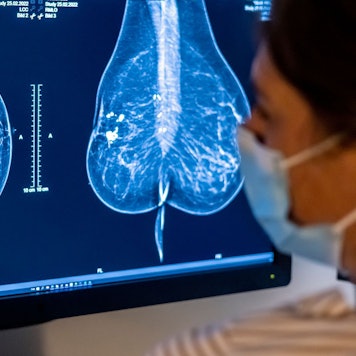

n der Diagnostik der Radiologie der Universitätsmedizin Rostock wird mit Hilfe der Magnetresonanztomographie ein Tumor festgestellt.

Copyright: Bernd Wüstneck/dpa-Zentralbild/dpa

Bei der Analyse von Bilddokumenten ist der Einsatz von KI-Technik am weitesten fortgeschritten, um beispielsweise in der Mammographie bessere, gezieltere Diagnostiken durchführen zu können. Man kann sich gut vorstellen, dass KI-Modelle schon jetzt so weit sind, dass diese Technologie demnächst die Ärzte unterstützt.